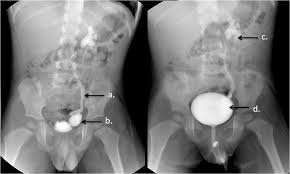

Digital X-Ray Services